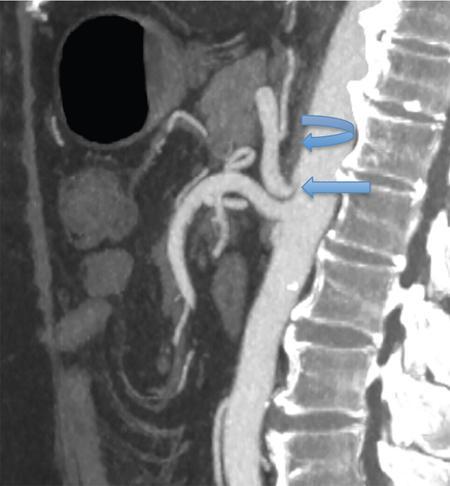

Celiac artery narrowing could be due to median arcuate ligament which is prominent diaphragmatic crura causing compression of the proximal celiac artery or it could be atherosclerotic. It is critical to distinguish median arcuate ligament syndrome from atherosclerosis, as the management of these conditions is completely different.

Diagnosis of median arcuate ligament syndrome before liver transplantation can help in formulating an appropriate surgical plan for division of the ligament during the transplant. It is best appreciated on arterial phase in sagittal reconstructed MIP (maximum intensity projection) images of CT angiography, seen as focal narrowing of the superior aspect of the proximal celiac trunk forming a hooked or ‘J’ appearance as seen in Fig. 9.14.7 (which is accentuated during end-expiration and lessens during end-inspiration), with poststenotic dilatation or evidence of collateral formation, in absence of associated atherosclerosis.